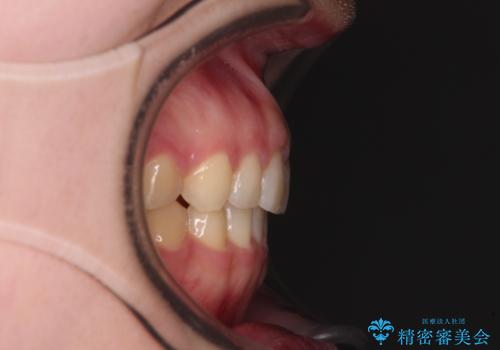

気になる残存乳歯と八重歯 ワイヤー矯正を併用したインビザライン治療

- 八重歯を気にして来院された患者様です。

八重歯のために乳歯が残存していたため、乳歯を抜去して八重歯となっている犬歯を歯列に収めることとしました。

八重歯の移動量が多くなるため、インビザラインと併用してワイヤー矯正を行い、八重歯を改善した後に、上下歯列をインビザラインで整えることとしました。

犬歯は歯根が長くて太いため移動に時間がかかる上に、周囲の歯が八重歯に寄ってきてしまうため、仕上がるまでに期間がかかりました。